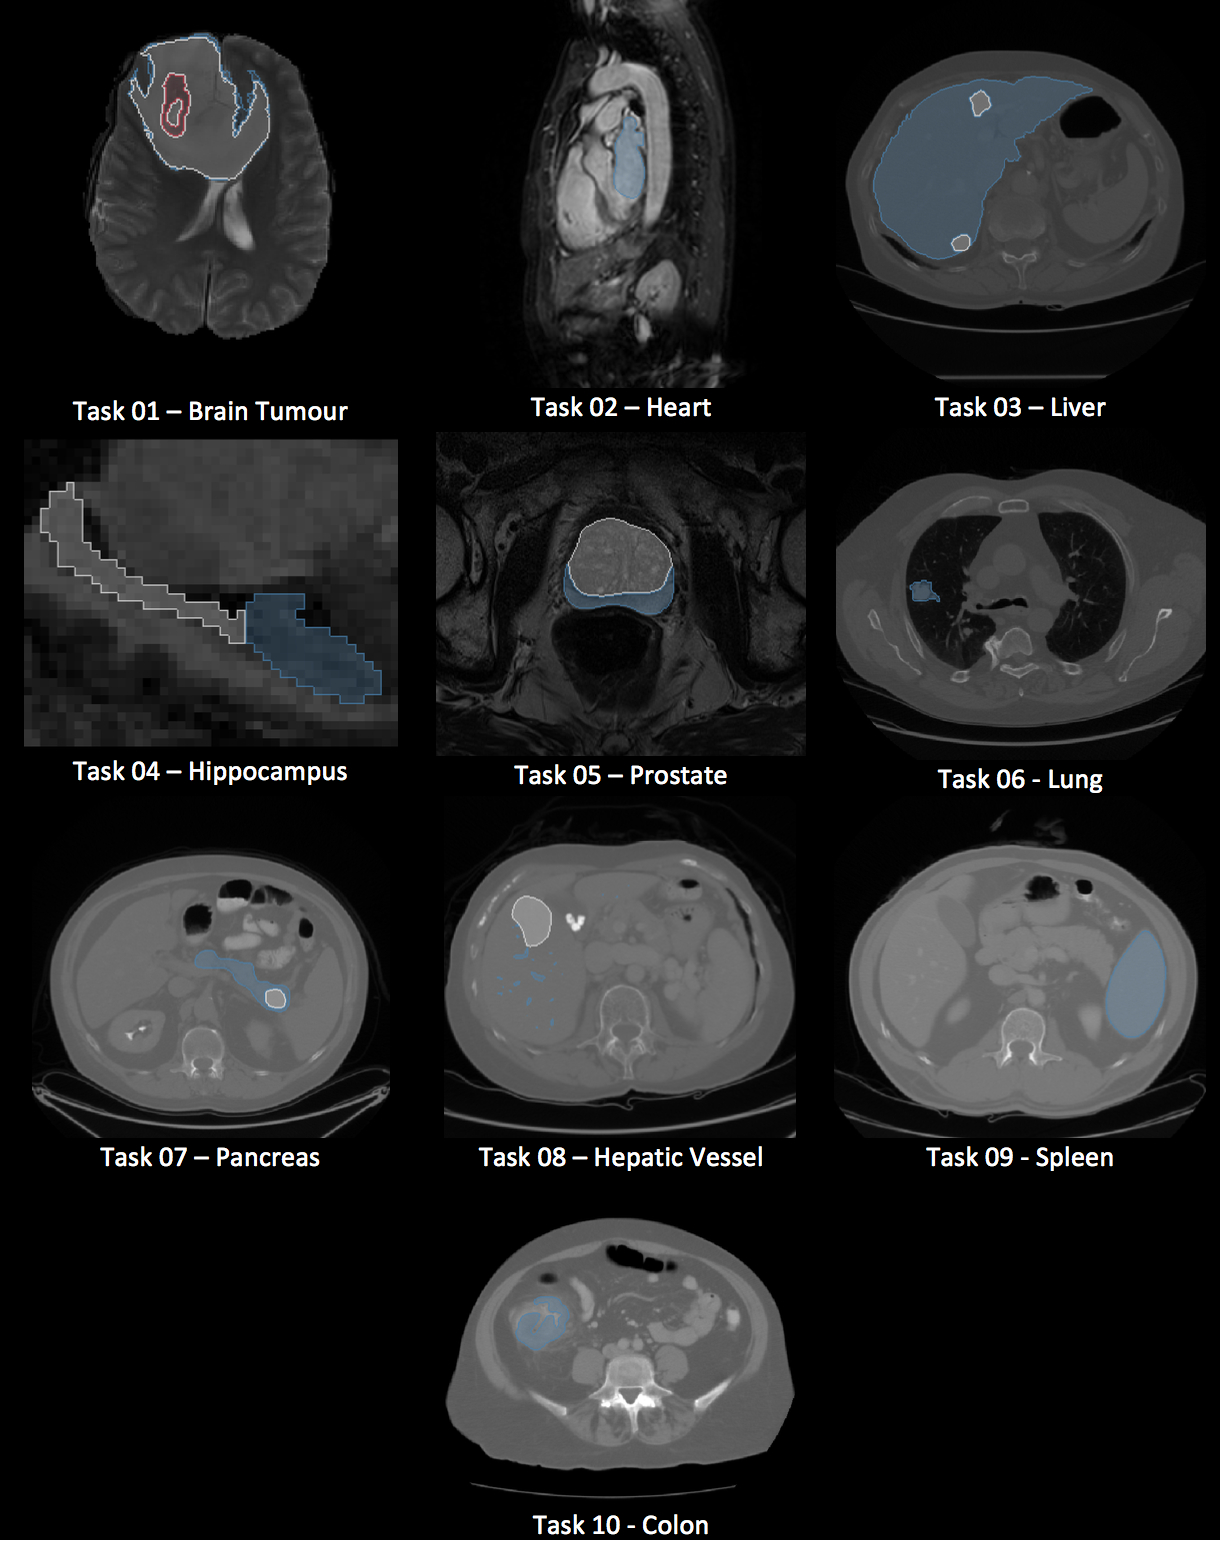

An overview of the ten datasets is provided in Table 1. The datasets were chosen based on availability and appropriateness for semantic segmentation algorithm development. The rationale for inclusion of each dataset is described in the table. Exemplar images and labels for each task are provided in Figure 1.

Refer to caption

Figure 1: Exemplar images and labels for each dataset. Blue, white, and red correspond to labels 1, 2, and 3, respectively, of each dataset. Not all tasks have 3 labels.